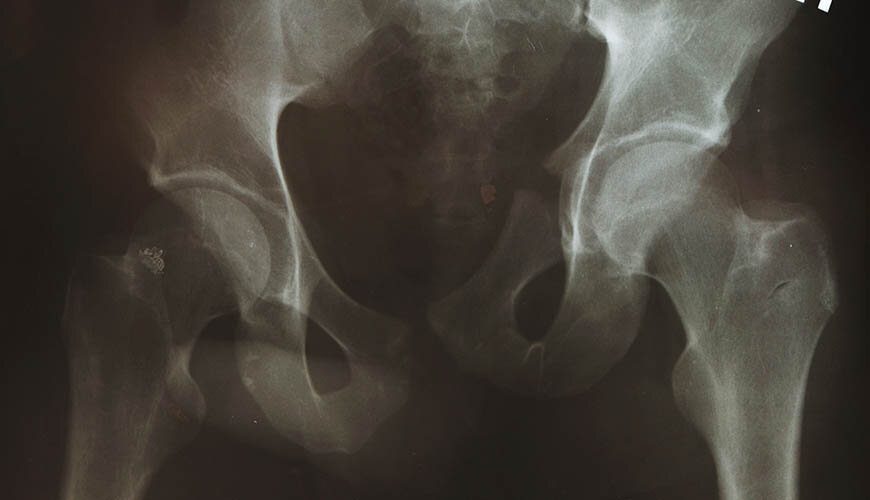

Hip arthritis is the fraying in the cartilages in the hip that causes loss of function with time. Hip arthritis causes pain and restriction of movement it often occurs due to old age and excessive weight though genetic factors might also play a role in its development. The common symptom of hip arthritis is pain while having long walks, standing for extended periods of time, and climbing the stairs. In advanced stages of arthritis, pain can break out even during short walks or while resting. The main purpose of hip arthritis treatment is to detect the situation while the disease is still mild and to prevent its progression. At this stage, non-surgical methods such as losing weight, resting, physiotherapy and medication therapy are used. However, if the arthritis has reached advanced stages with progressive and severe complaints, total hip arthroplasty (replacement) surgery may become necessary.

In addition to arthritis, total hip arthroplasty is also performed for the treatment of hip fractures and avascular necrosis. It is not possible for a certain part of the fractured neck of femur (thighbone) to united once fractured. In hip fractures, therefore, surgeons extract and replace the fractured section with a prosthetic supplement that carries out the function of the hip joint. In avascular necrosis, on the other hand, the vascular structure that feeds the head of the hip joint loses its function and causes the death and collapse of the living part of the bone head. This is why advanced stages of avascular necrosis may require prosthetic treatment.

Total hip arthroplasty is an open surgical procedure and takes about 2 hours in average. As the operation requires attention, expertise, and precision, it can only bear successful results under the command of expert surgeons and use of advanced technologies. The operation is mostly performed under general anaesthesia. Prosthetics type to be used is determined in accordance with the requirements of the patient’s case, age, hip structure, and the stage of disease arthritis. The operation starts with a 10cm incision and the extraction of the spherical section called the femoral head. Next the surgeon carves the acetabular socket, a concave surface of the pelvis and inserts the acetabular prosthetic into the carved area. This is followed by rasping the inner side of the femur and placing the femoral prosthetic.